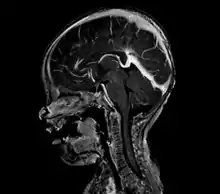

| Large arteriovenous malformation of the parietal lobe | |

vein of Galen malformation

A cerebral AVM diagnosis is established by neuroimaging studies after a complete neurological and physical examination.[5][12] Three main techniques are used to visualize the brain and search for an AVM: computed tomography (CT), magnetic resonance imaging (MRI), and cerebral angiography.[12] A CT scan of the head is usually performed first when the subject is symptomatic. It can suggest the approximate site of the bleed.[3] MRI is more sensitive than CT in the diagnosis, and provides better information about the exact location of the malformation.[12] More detailed pictures of the tangle of blood vessels that compose an AVM can be obtained by using radioactive agents injected into the blood stream. If a CT is used in conjunction with an angiogram, this is called a computerized tomography angiogram; while, if MRI is used it is called magnetic resonance angiogram.[3][12] The best images of a cerebral AVM are obtained through cerebral angiography. This procedure involves using a catheter, threaded through an artery up to the head, to deliver a contrast agent into the AVM. As the contrast agent flows through the AVM structure, a sequence of X-ray images are obtained.[12]